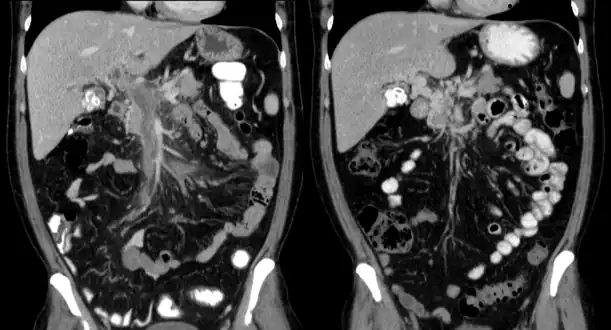

Computed tomography scan showing portal vein thrombosis (with cavernous change of portal vein )

Portal vein thrombosis on computed tomography (left) and cavernous transformation of the portal vein after 1 year

The diagnosis of portal vein thrombosis is usually made with imaging confirming a clot in the portal vein; ultrasound is the least invasive method and the addition of Doppler technique shows a filling defect in blood flow. PVT may be classified as either occlusive or nonocclusive based on evidence of blood flow around the clot.[5] An alternative characterization based on site can be made: Type 1 is limited to the main portal vein, Type 2 involves only a portal vein branch (2a, or 2b if both branches are affected), and Type 3 if clot is found throughout both areas.[8] Determination of condition severity may be derived via computed tomography (CT) with contrast, magnetic resonance imaging (MRI), or MR angiography (MRA). Those with chronic PVT may undergo upper endoscopy (esophagogastroduodenoscopy, EGD) to evaluate the presence of concurrent dilated veins (varices) in the stomach or esophagus.[3] Other than perhaps slightly elevated transaminases, laboratory tests to evaluate liver function are typically normal.[1] D-dimer levels in the blood may be elevated as a result of fibrin breakdown.